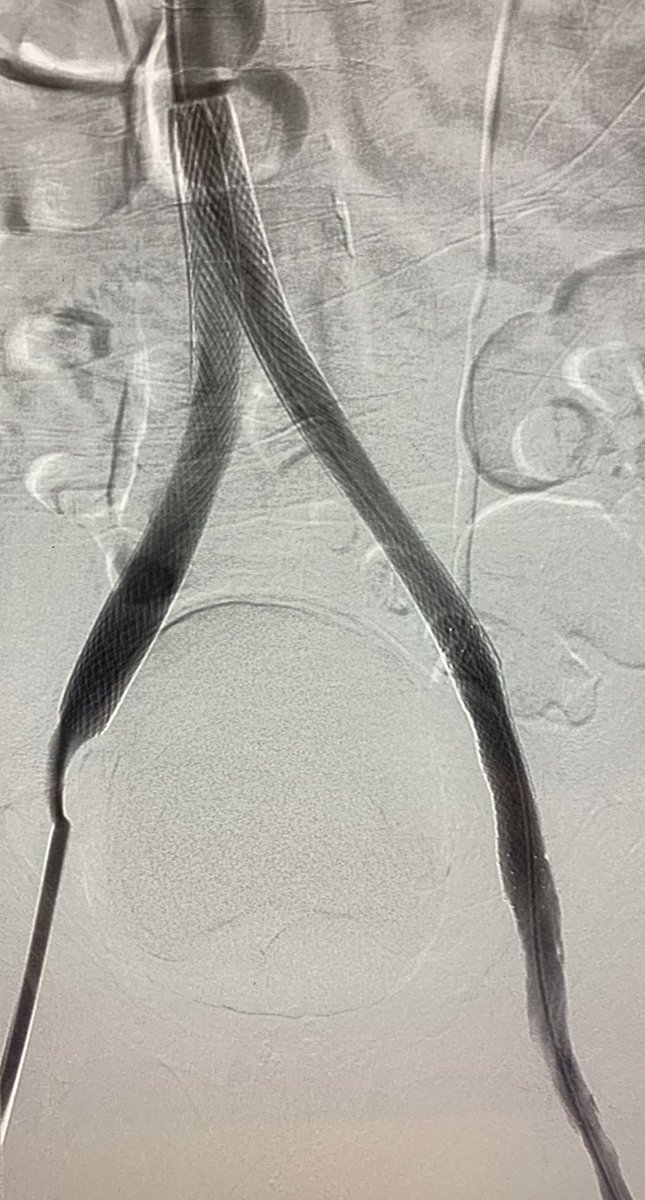

3 month old #IVCfilter with iliocaval occlusion, bilateral leg edema. Crossed both CIV occlusion from below, forceps #Filterout with 18Fr sheath then 18mm wallstent iliocaval reconstruction. #WeCanRecan